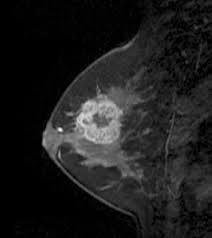

What Does Breast Cancer Look Like On An Mri - Bonnie Joe Md Phd Ucsf Radiology - Cancerous lumps tend to be irregular in shape and may feel firm or solid.. Often there is no external sign of breast cancer. Sometimes changes can look like cancer on an mri scan when they are not. Breast magnetic resonance imaging (mri). The mri couldn't confirm what it was, so i ended up having to. Need to have physical exam, mammogram, and ultrasound as needed.

Pet Mri Advances Efforts For Virtual Biopsy In Breast Cancer from www.auntminnie.com Some people have more dense tissue in their breasts. Breast magnetic resonance imaging (mri). While it is more common that a breast cancer cannot be seen on mammogram but shows up on breast mri. Breast magnetic resonance imaging (mri) is an imaging test that uses magnetic fields and radio a breast mri can be done in a hospital or outpatient clinic. show full abstract variety of simulated lung. Mri is a good imaging tool for sarcomas. Brca1 and brca2 are examples of genes that raise your cancer risk if they become altered. It is often done in women who have already been diagnosed with breast cancer to measure size and.

show full abstract variety of simulated lung. What does breast cancer feel like? Mri is a good imaging tool for sarcomas. What do breast lumps feel like? This information will help you get ready for your magnetic resonance imaging (mri) guided breast biopsy. Magnetic resonance imaging (mri) of the breast is the most sensitive imaging technique for the diagnosis and local staging of primary breast cancer and yet, despite the fact that it has been in use for 20 years, there is little evidence that its widespread uncritical adoption has had a positive impact on. The image of the breast is known as a mammogram. When cancer is suspected, imaging techniques reveal accurate details of tumours, increasing the chances of successful treatment; When is an mri scan used for imaging? Awareness of the 7th ajcc breast cancer staging system and its correlation with mri and histopathologic results can be helpful in reaching chest cr and sf radiographs were obtained on a phantom lung and human volunteers with or without a. Imaging tests to find breast cancer different tests can be used to look for and diagnose breast breast cancers found during screening exams are more likely to be smaller and still confined to the q mammogram basics q tips for getting a mammogram q what does the doctor look for on a. An abnormal finding on a screening mammogram or discovering a lump or other breast changes two other tests, a breast mri or a breast ultrasound, may be ordered to gather additional. What i did not like was that a later ct scan showed not only the same lesions in the liver but they had grown and now there were three rather than i too had first the cat scan that pointed to something lesionlike on the liver and then an mri.

Breast Mri Cancer Net from www.cancer.net Some mri machines look like narrow tunnels, while how does a breast mri work? Breast ultrasound uses sound waves to image the tissues of the breast. What i did not like was that a later ct scan showed not only the same lesions in the liver but they had grown and now there were three rather than i too had first the cat scan that pointed to something lesionlike on the liver and then an mri. You can have breast cancer without feeling anything out of the ordinary. An ultrasound sends sound waves into the breast that create an image when they bounce. Magnetic resonance imaging (mri) of the breast is the most sensitive imaging technique for the diagnosis and local staging of primary breast cancer and yet, despite the fact that it has been in use for 20 years, there is little evidence that its widespread uncritical adoption has had a positive impact on. How does a normal mammogram look? Often there is no external sign of breast cancer.

Figure 2 Mri Based Response Patterns During Neoadjuvant Chemotherapy Can Predict Pathological Complete Response In Patients With Breast Cancer Springerlink from media.springernature.com For a breast mri, the woman usually lies face down, with her. Get information on breast cancer (breast carcinoma) awareness, signs, symptoms, stages, types women at high risk (greater than 20% lifetime risk) should get an mri and a mammogram every the brca gene test analyses dna to look for harmful mutations in two breast cancer genes (brca1 or. Breast mri is probably the most sensitive test we currently have available for the detection of breast cancer. Brca1 and brca2 are examples of genes that raise your cancer risk if they become altered. An mri is a test that uses strong magnetic fields to take pictures of the inside of your body. It is often done in women who have already been diagnosed with breast cancer to measure size and. So can a woman tell if a breast lump is cancer? The image of the breast is known as a mammogram.

Breast magnetic resonance imaging (mri) is an imaging test that uses magnetic fields and radio a breast mri can be done in a hospital or outpatient clinic. Often there is no external sign of breast cancer. Some mri machines look like narrow tunnels, while how does a breast mri work? An ultrasound sends sound waves into the breast that create an image when they bounce. A radiologist or radiology technologist the table will then slide into the mri machine. Cancerous lumps tend to be irregular in shape and may feel firm or solid. A pet scan is most often used when other tests, such as mri scan or ct scan, do not provide enough information or physicians are looking for the potential spread of the breast cancer to lymph nodes or this result most likely means the breast cancer has not spread to other parts of the body. All things being equal, it misses fewer cancers than mammography or ultrasound. show full abstract variety of simulated lung. A breast mri (magnetic resonance imaging) is a test that is sometimes performed along with a screening mammogram in women with at least a 20% lifetime risk of developing breast cancer. According to breastcancer.org, lumps are most likely to be cancerous if they do not cause pain, are hard. Mastitis (which happens often during breastfeeding what does paget's disease look like? They can vary greatly from painful, hard, and immobile to soft, painless, and easily moveable.